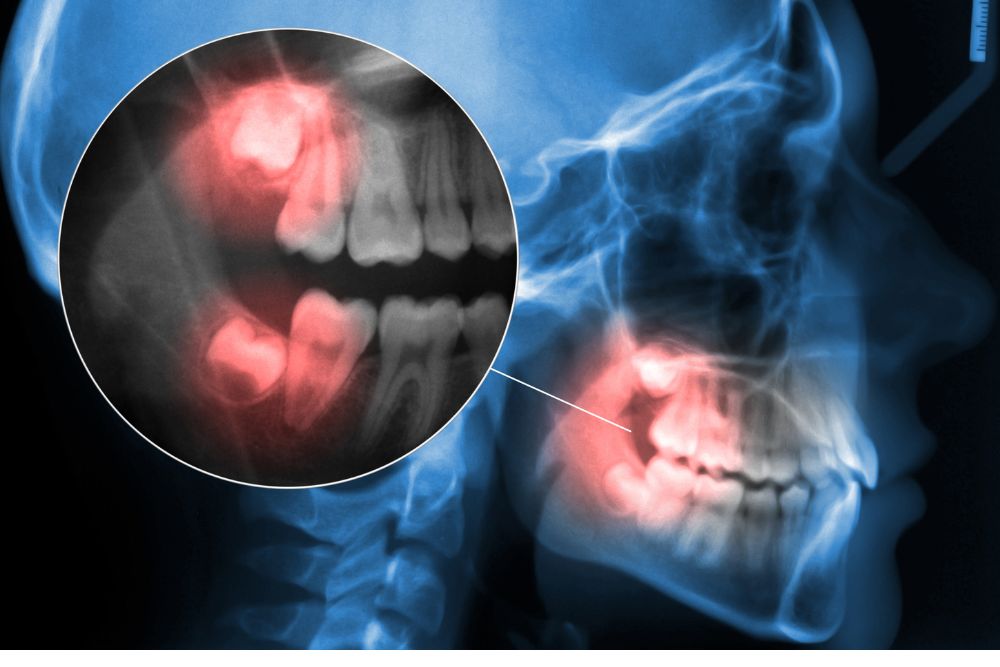

Impacted Wisdom Tooth Extraction: What It Is, Why It’s Needed, and What to Expect

The extraction is done in dental offices, by the dentist or dental surgeon under local or general anesthesia.